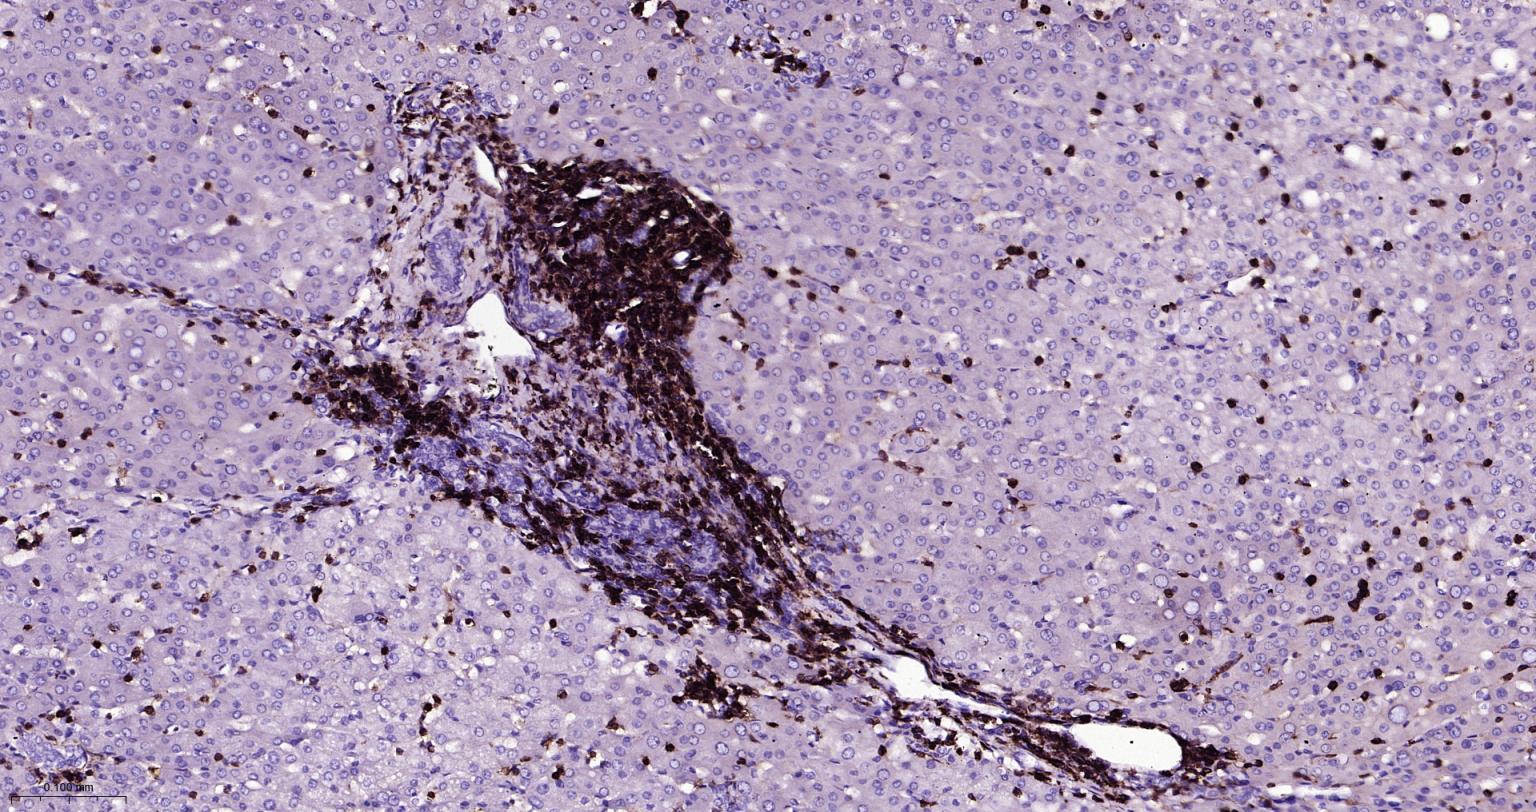

Paraformaldehyde-fixed, paraffin embedded Human Spleen; Antigen retrieval by boiling in sodium citrate buffer (pH6.0) for 15 min; Antibody incubation with CD45 Monoclonal Antibody, Unconjugated(bsm-54757R) at 1:200 overnight at 4°C, followed by conjugation to the bs-0295G-HRP and DAB (C-0010) staining.